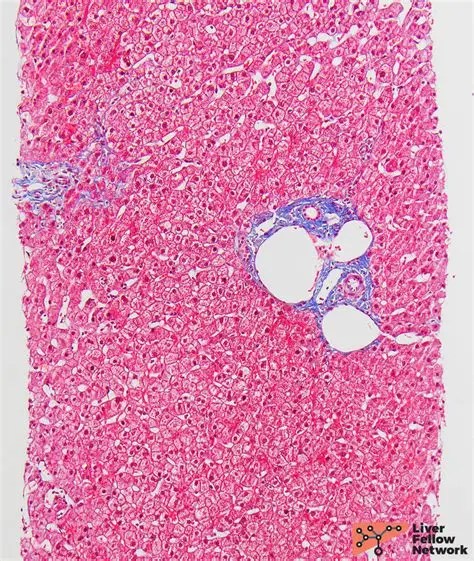

HE/IHC

Histopathology